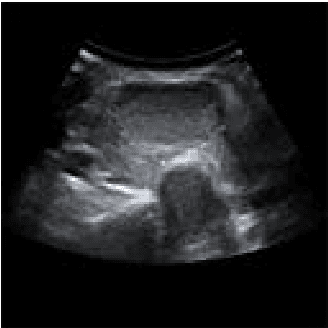

The incidence of thyroid nodule is very high and generally increases with the age. Thyroid nodule may presage the emergence of thyroid cancer. The thyroid nodule can be completely cured if detected early. Fine needle aspiration cytology is a recognized early diagnosis method of thyroid nodule. There are still some limitations in the fine needle aspiration cytology, and the ultrasound diagnosis of thyroid nodule has become the first choice for auxiliary examination of thyroid nodular disease. If we could combine medical imaging technology and fine needle aspiration cytology, the diagnostic rate of thyroid nodule would be improved significantly. The properties of ultrasound will degrade the image quality, which makes it difficult to recognize the edges for physicians. Image segmentation technique based on graph theory has become a research hotspot at present. Normalized cut (Ncut) is a representative one, which is suitable for segmentation of feature parts of medical image. However, how to solve the normalized cut has become a problem, which needs large memory capacity and heavy calculation of weight matrix. It always generates over segmentation or less segmentation which leads to inaccurate in the segmentation. The speckle noise in B ultrasound image of thyroid tumor makes the quality of the image deteriorate. In the light of this characteristic, we combine the anisotropic diffusion model with the normalized cut in this paper. After the enhancement of anisotropic diffusion model, it removes the noise in the B ultrasound image while preserves the important edges and local details. This reduces the amount of computation in constructing the weight matrix of the improved normalized cut and improves the accuracy of the final segmentation results. The feasibility of the method is proved by the experimental results.